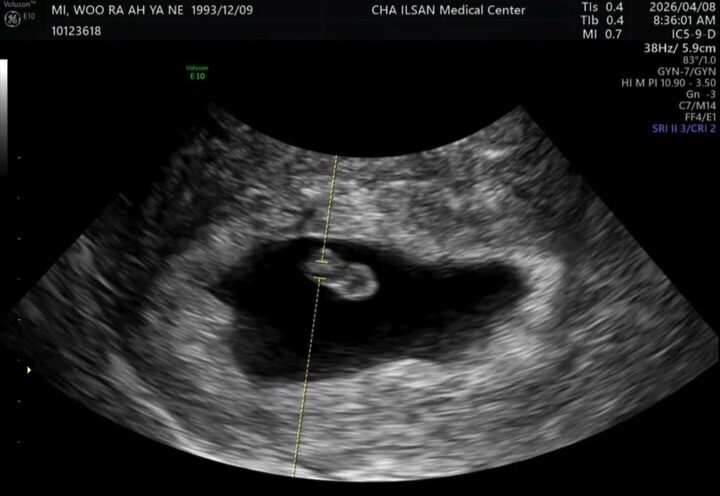

Alongside an ultrasound photo, Ayane joyfully announced, “I finally got to meet Bokboki (the nickname for the baby).” She added, “We will soon become a family of four,” expressing happiness and anticipation by adding “Bokboki” to a warm family photo.

Finally, Ayane expressed her emotional feelings, “It’s been about 8 weeks now, and Bokboki is growing well. I’m fighting morning sickness, but even that I’m thankful for.” She revealed her current severe morning sickness, saying, “It’s been about 10 days since the morning sickness started and I lost 2kg. I haven’t vomited, but I just don’t want to eat. I’m hungry but my stomach feels bad.”